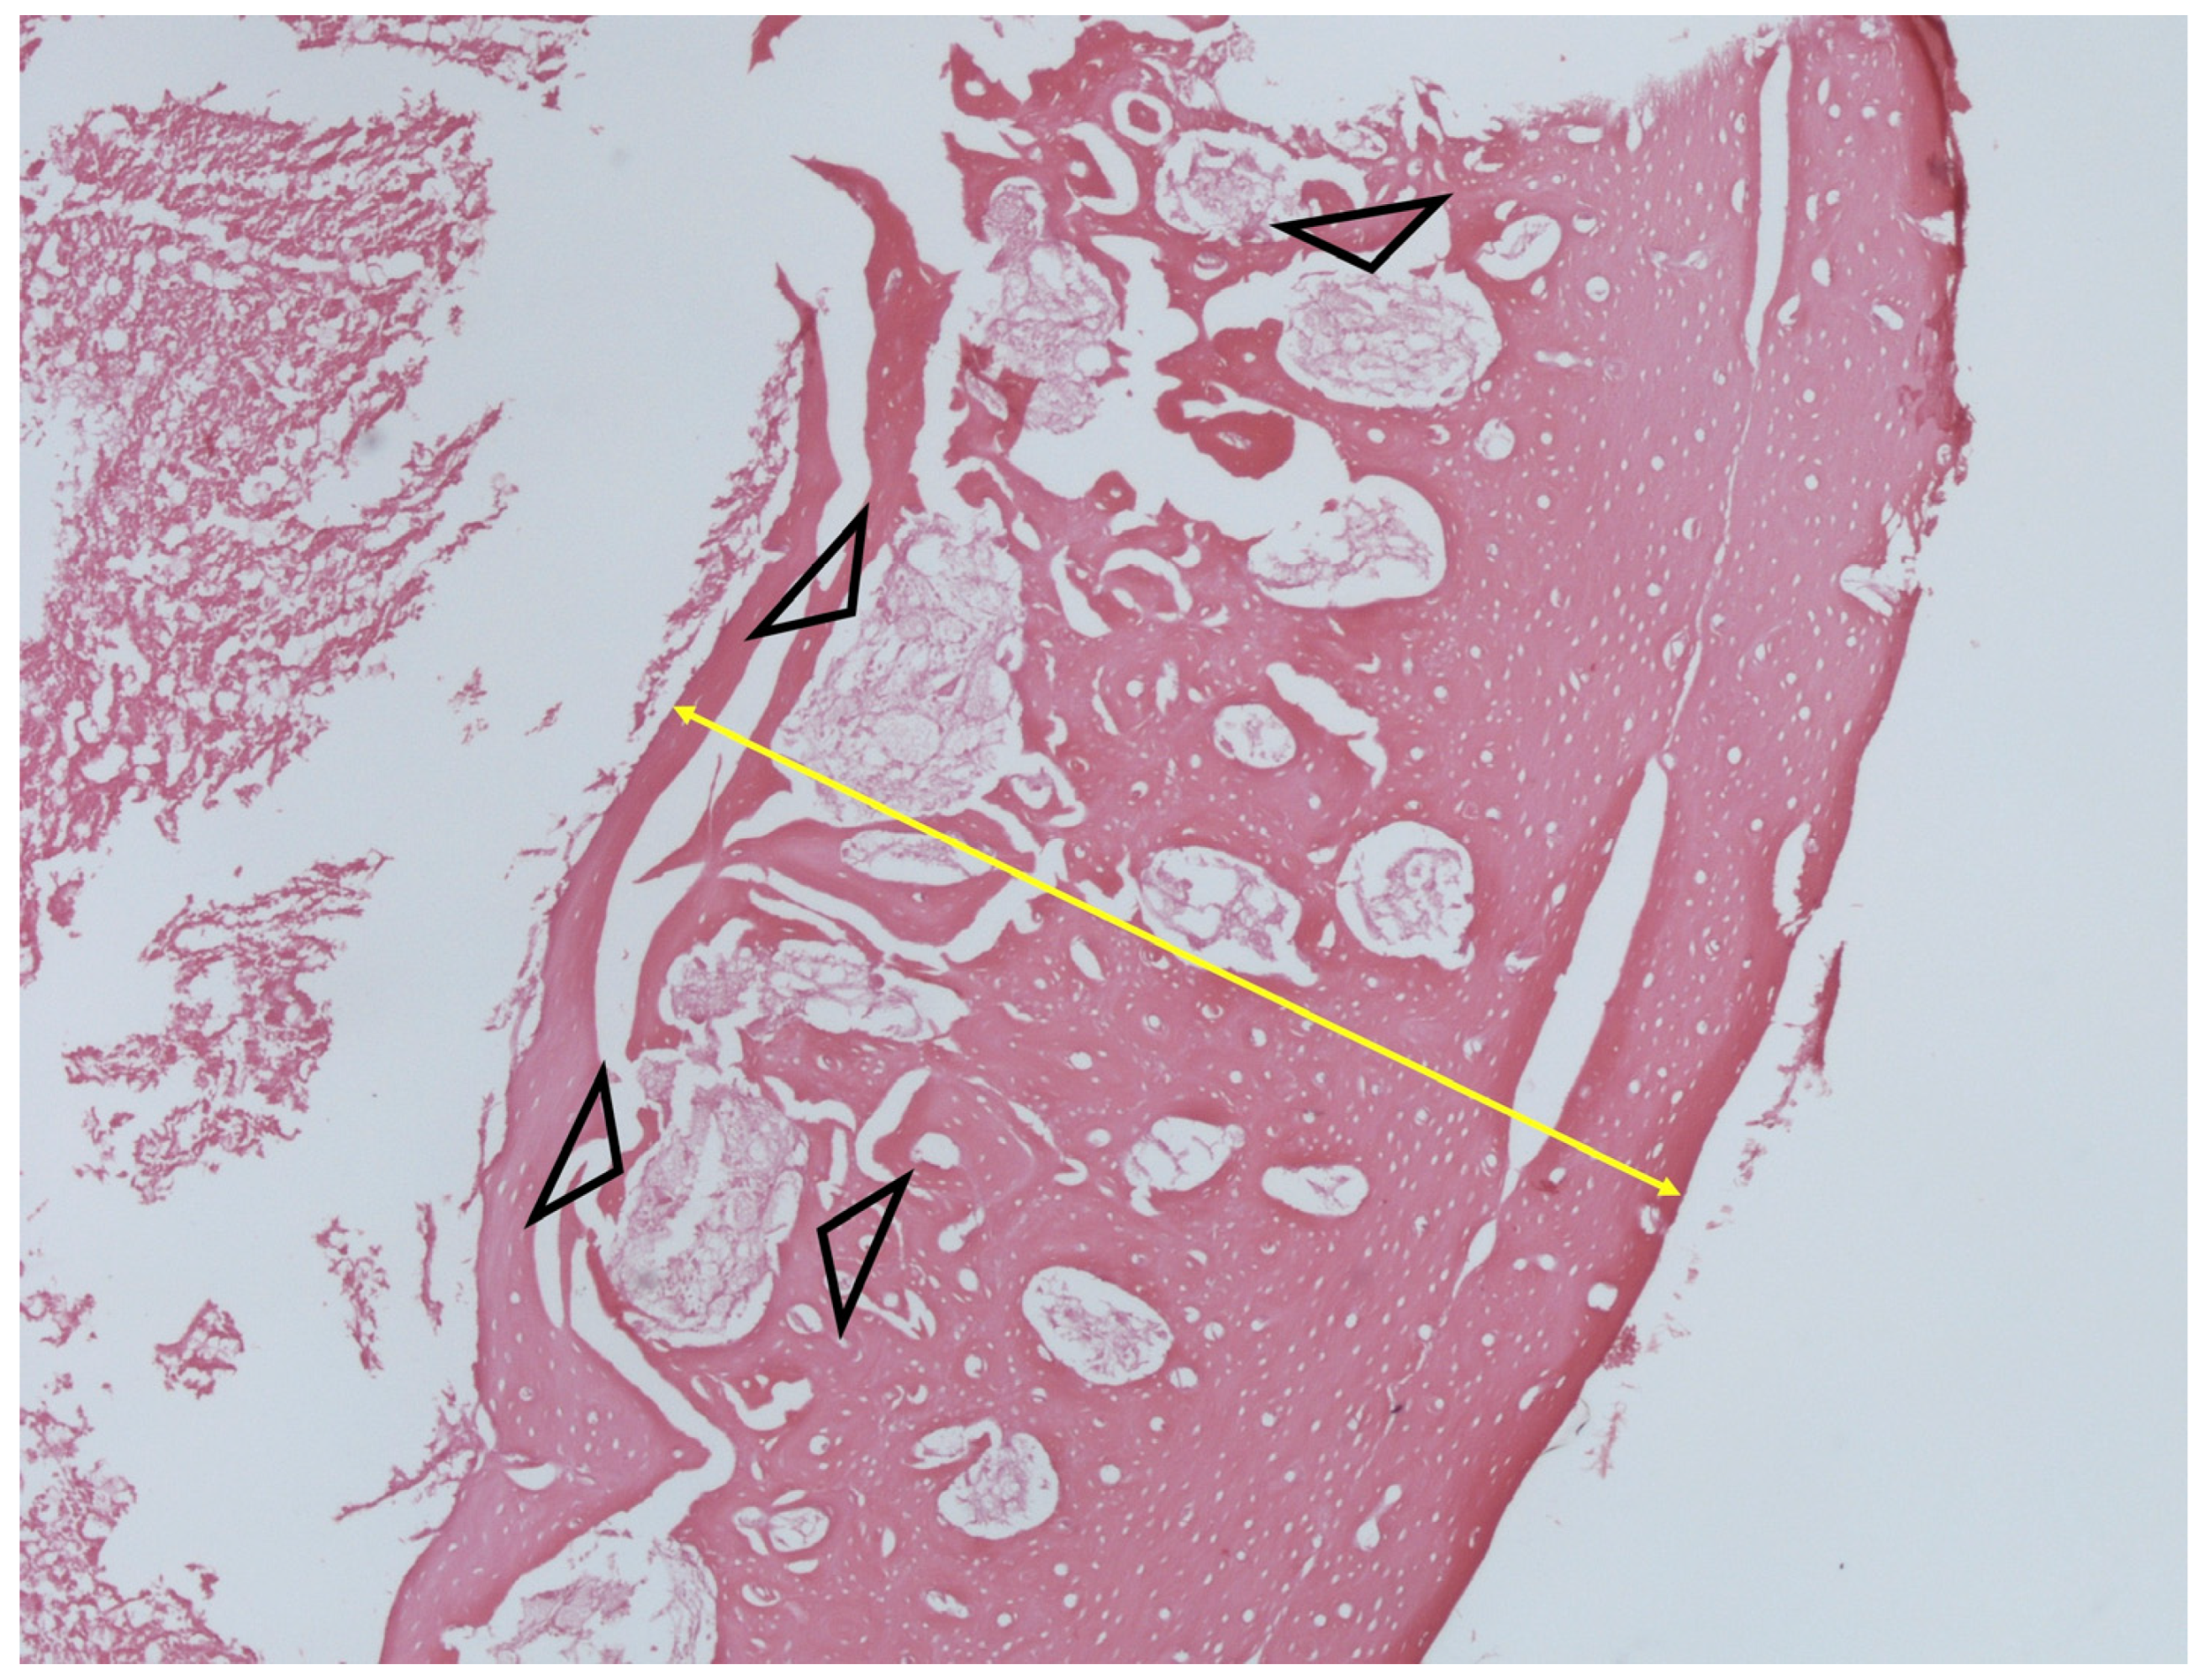

2.9. Histology

3.5. Histology